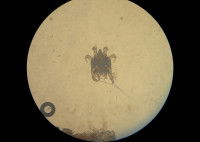

Le responsable de la gale auriculaire est un acarien répondant au nom de Otodectes cynotis. Il passe toute sa vie sur l'animal qu'il parasite, vivant en surface du conduit auditif. Ses repas sont constitués de débris d'épiderme et de cérumen. A leur tour, ses larves pondent des oeufs, qui produisent d'autres adultes, et ainsi de suite. C’est cette prolifération du parasite qui provoque des inflammations.

L’absence de cérumen ne permet pas de conclure à l'absence de cette maladie canine parasitaire. En effet, ce dernier n'est pas toujours présent, et il faut parfois effectuer un prélèvement assez profond pour mettre en évidence le parasite. Le vétérinaire pourra le détecter au microscope.